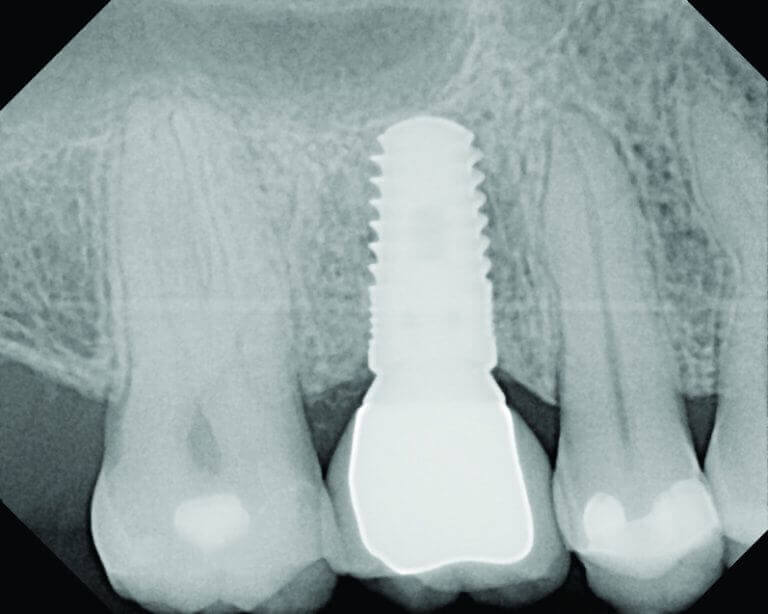

Zobni vsadek z zdravo okoliško kostjo

Vstavitev vsadka je tisti del terapije, ki ponavadi najbolj zanima pacienta. Poseg ni boleč, saj se opravi pod lokalno anestezijo. Terapevt odgrne dlesen in s posebnimi svedri pripravi ležišče za vsadek v kost. V ležišče nato vstavi zobni vsadek primerne velikosti in čezenj zašije dlesen. Tako se lahko začne celjenje in integracija vsadka s kostjo, ki se obraste okoli navojev. Poseg traja 30—60 minut, medtem ko traja celjenje od tri do šest mesecev. V tem času je pacient še vedno brez krone zoba in po potrebi nosi začasen protetični nadomestek.

Kadar se odločate za vsadek, morate vedeti, da je to le del, ki nadomešča korenino zoba in je očem neviden. Na to »umetno korenino« je nato treba namestiti še zobno krono. Ta pride na vrsto šele potem, ko je celjenje zaključeno in je zobni vsadek vraščen v kost.